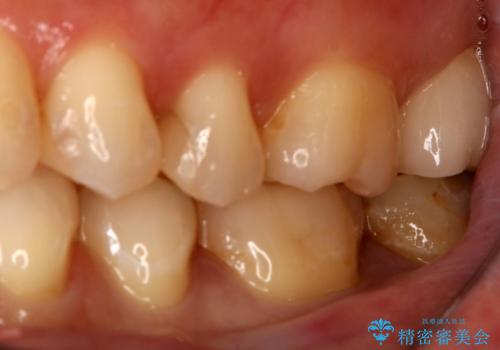

- 左下6、7番の虫歯をセラミックにて治療を希望された患者様です。

切削量を考慮してセラミックインレーを選択しました。

7番は虫歯が深かったのでCR裏層した上で形成、印象をしています。